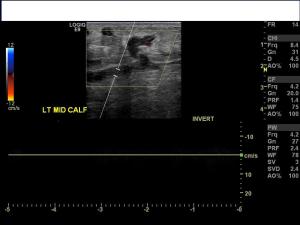

History: 60 year old female with lower extremity pain, swelling, and redness.

This is a case of superficial thrombophlebitis, which is an inflammatory-thrombotic disorder of the superficial venous system. Typically it presents with pain, swelling, and warmth in the lower extemities with a “palpable cord,” which represents a thrombosed vein, as in the image above. When thrombophlebitis occurs in the breast, it is called Mondor Disease.

There is a risk of extension of clot into the deep venous system of the legs, and possible pulmonary embolism.